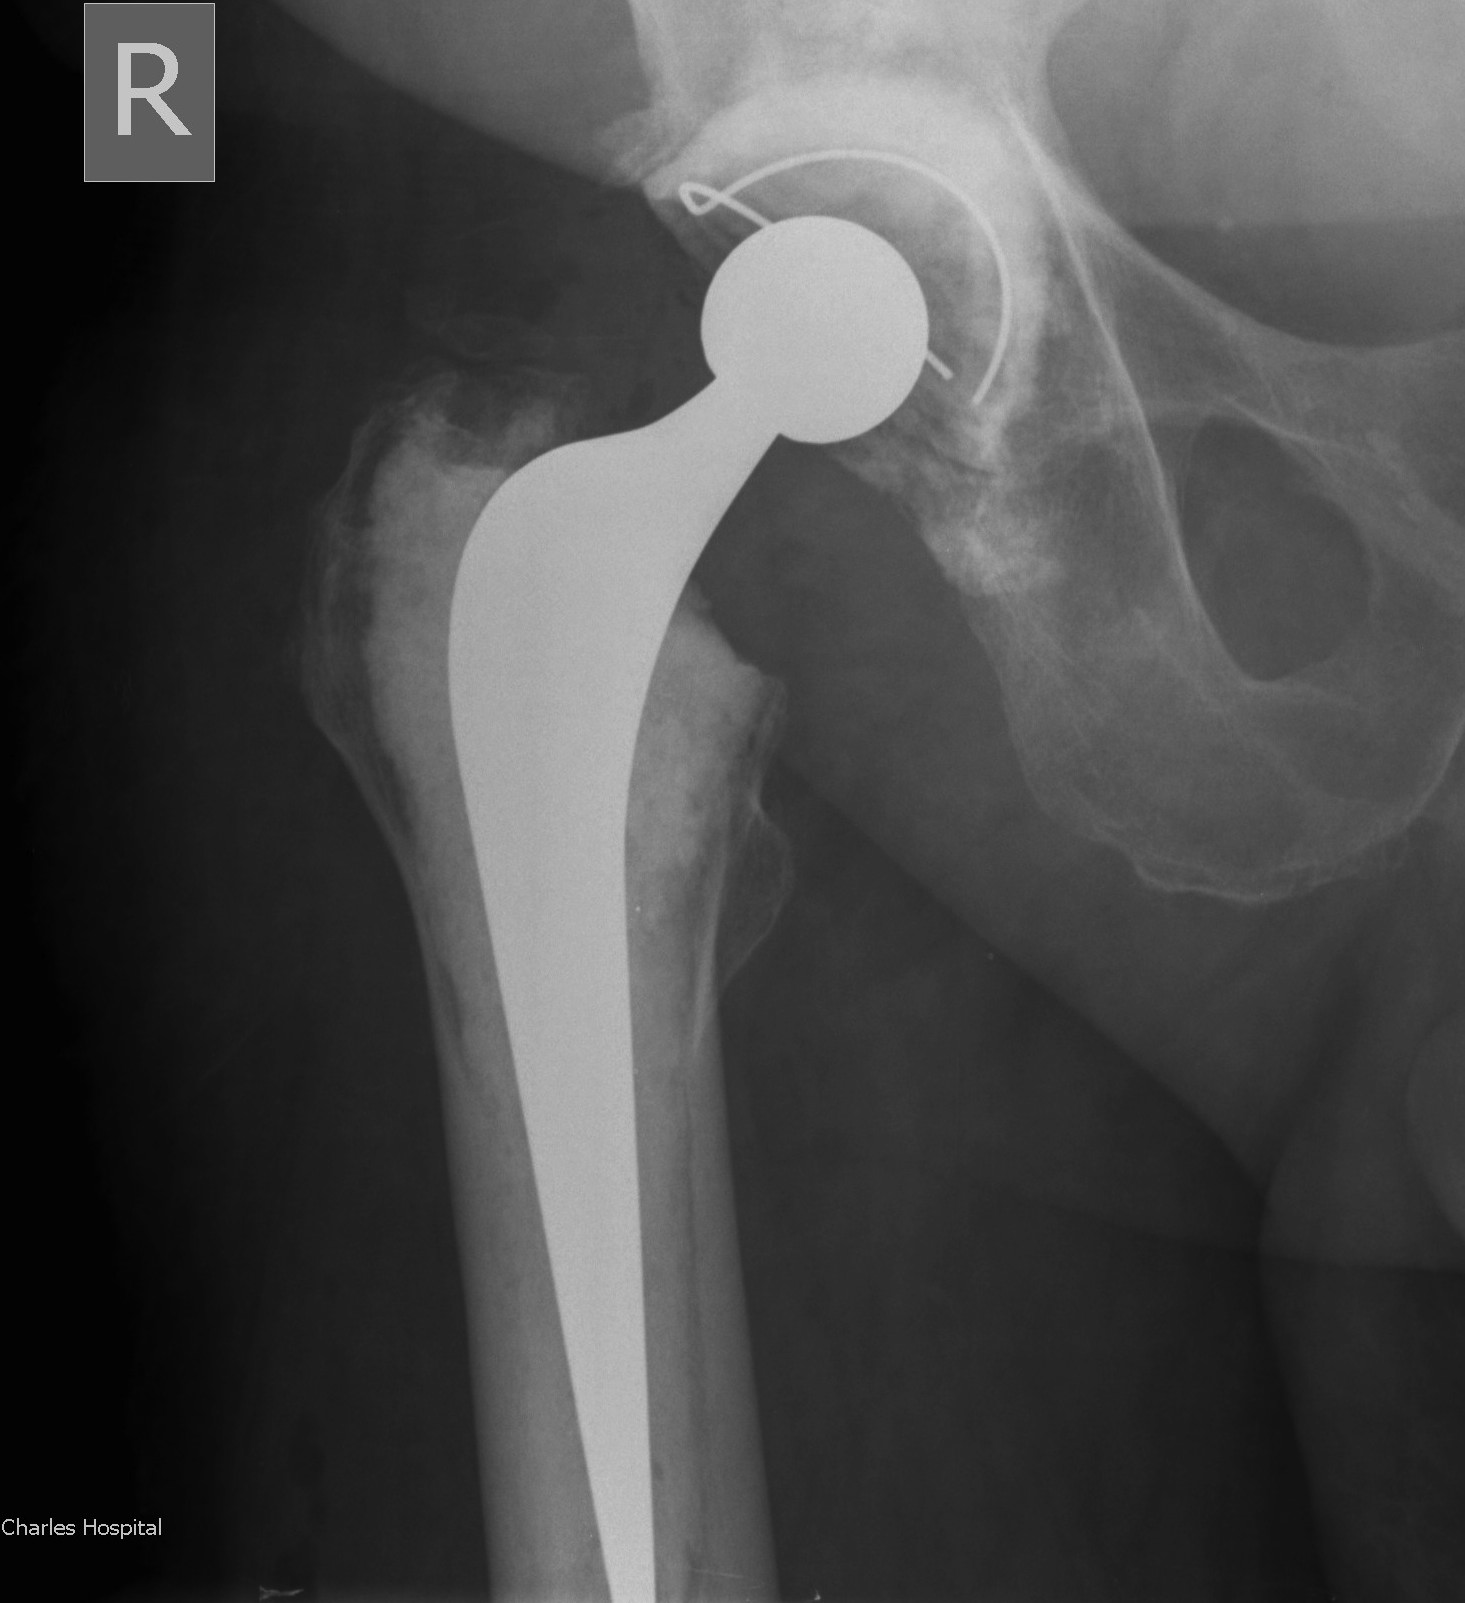

Two-Stage Revision

Technique

First stage

- debridement + removal of implants and all cement

- insert antibiotic impregnated cement spacer

Types of spacers

- hand made +/- metal reinforcement

- moulds +/- metal reinforcement

- prefabricated

- antibiotic-coated prosthesis

Ball antibiotic cement Mold

Prefabricated Handmade

Zimmer StageOne Select Hip Cement Spacer Molds